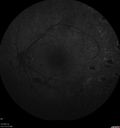

20 year old mane with fresh vitreous hemorrhage in the right eye. At age 15 he had a PPV and laser in the left eye and laser in the right eye. The vision is OD 20/80 PH 20/25, OS 20/25. The left eye has a mild cataract. He had prior testing for coagulopathies which was negative. Testing done for syphillis and TB was negative. Additional laser was done to prevent further bleeding in the right eye.